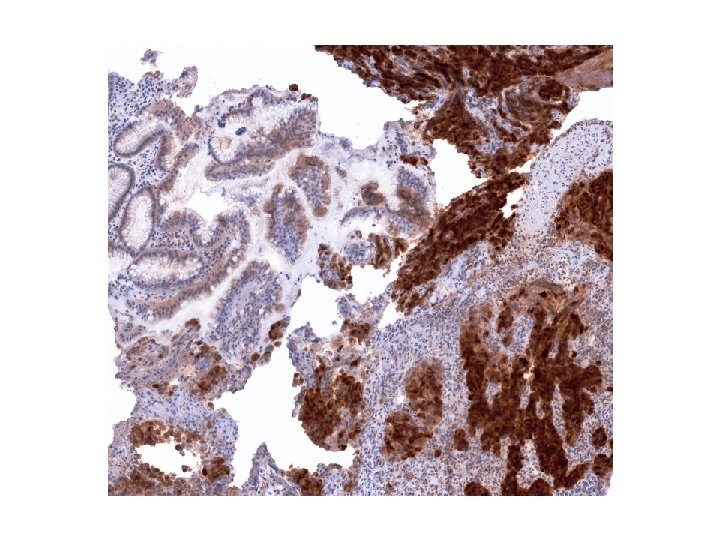

Imunohistologický nález nádorových buněk • K vyloučení nediferencovaného karcinomu vyšetřeny cytokeratiny, skupinovitě (AE 1/AE

Imunohistologický nález nádorových buněk • K vyloučení nediferencovaného karcinomu vyšetřeny cytokeratiny, skupinovitě (AE 1/AE 3), i jednotlivě, reakce nádorových buněk bylanegativní. • Také reakce na CD 117 na možný stromálmí nádor byla negativní. • Reakce na S 100 protein byla slabá, ale zřetelně pozitivní, silně pozitivní reakce byla na Melan A i na HMB 45.

Diagnostický závěr • Pozitivní reakce na Melan A a na S 100 protein svědčí

Diagnostický závěr • Pozitivní reakce na Melan A a na S 100 protein svědčí pro dg. maligního melanomu, negativní reakce na cytokeratiny a CD 117 vyloučily nediferencovaný karcinom a maligní stromální tumor. • Je tento nádor primární?